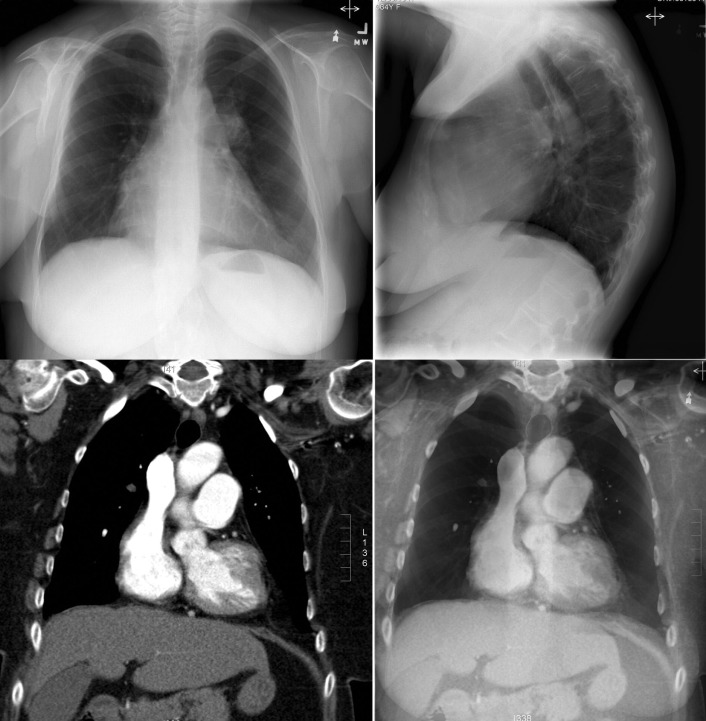

Chest radiographs depicting cardiomegaly. The anteroposterior radiograph shows some increase of the curvature of the right atrium and enlargement of the main pulmonary artery. The lateral chest radiograph shows a significant increase in the apposition of the right ventricle to the sternum, albeit in a patient with severe kyphosis. The contrast-enhanced computed tomography (CT) scan in the left lower image reveals the enlargement of the right atrium and the main pulmonary artery. The superimposition of the coronal CT scan on that of the anteroposterior chest radiograph is depicted in the right lower image, corroborating the impression of enlargement of the pulmonary artery appreciated on the chest radiograph.